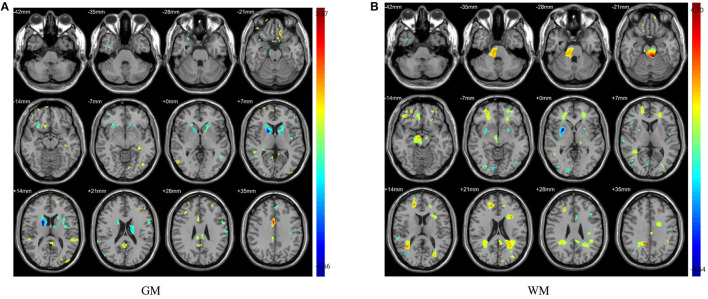

The distinguished brain regions on WM identified by machine learning have been shown in Figure 5 and reported based on AAL listed in Supplementary Table S6. The common regions found by four feature selection include PoCG, ORBmid, SFGdor, IOG, and LING. Except for SFGdor and LING, other regions have been reported in previous findings. The results detected by statistical analysis have been listed in Supplementary Table S4 and shown in Figure 3. Similarly, most regions also have been found by machine learning methods, while some small regions have not been found, such as INS (cluster size = 99), IPL (cluster size = 109), ANG (cluster size = 47), IFGoperc (cluster size = 39), and SPG (cluster size = 57).

Figure 3.

The abnormal brain regions identified by two sample t-test. Color bars indicate t-value. (A) Abnormal regions of GM; (B) Abnormal regions of WM.